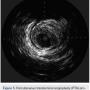

After undertaking initial medical optimization, the patient continued to have extensive symptoms with consumption of 5-6 nitroglycerin tablets (NTGs) on bad days and 2 NTGs on good days. Intravascular ultrasound (IVUS) of the LM was undertaken and this revealed a minimal lumen area (MLA) of 5.0 mm2, consistent with a significant LM stenosis (Figure 4). He was referred for coronary artery bypass grafting, but was felt to be a poor candidate due to his poor left ventricular (LV) systolic function. Therefore, we decided to undertake percutaneous coronary intervention (PCI) of his LAD and/or LM. The overall risk of complications of about 5-6% or so was discussed with patient, including the likely need for hemodynamic support.